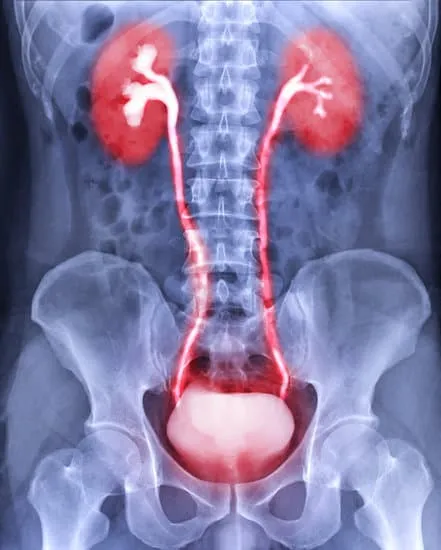

Dr.K.Seethalakshmi is the senior Urogynaecologist in addition to Obstetrician & Gynaecologist with 27 years of experience in OBG & 20 years of experience in Urogynaecology. She is an expert in Advanced Urogynaecology and Female Pelvic floor Reconstructive surgeries

Urogynaecology focusses on the management of Female Pelvic Floor disorders, which include Pelvic organ prolapse, Urinary incontinence, pelvic pain and recurrent urinary tract infections, Faecal incontinence& female sexual dysfunction.